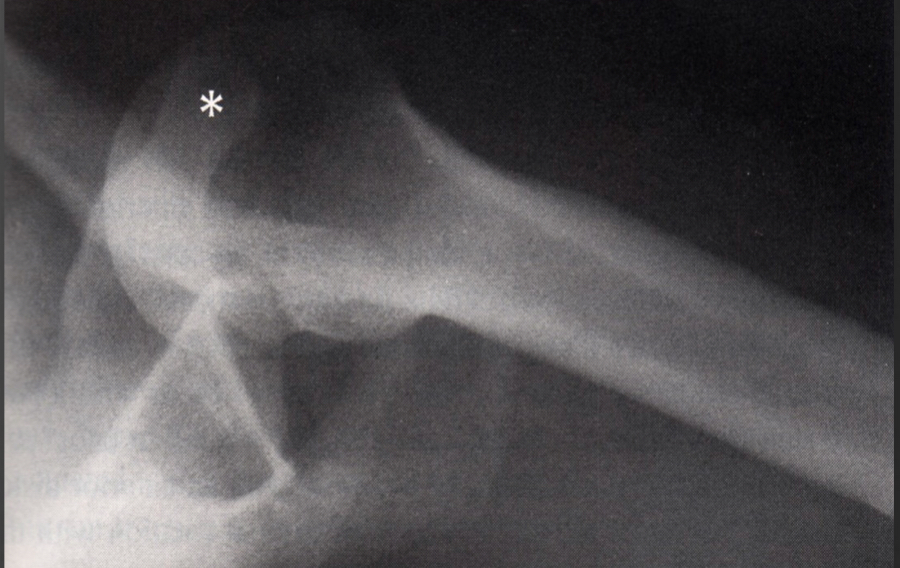

Luxatio Erecta is what kind of fx

Uncommon but distinct shoulder dislocation

● Inferior glenohumeral dislocation

● Arm abducted - held above head, can’t move it (“arm up”)

Humeral head impingement under anterior glenoid rim

○ Predisposes to future dislocations